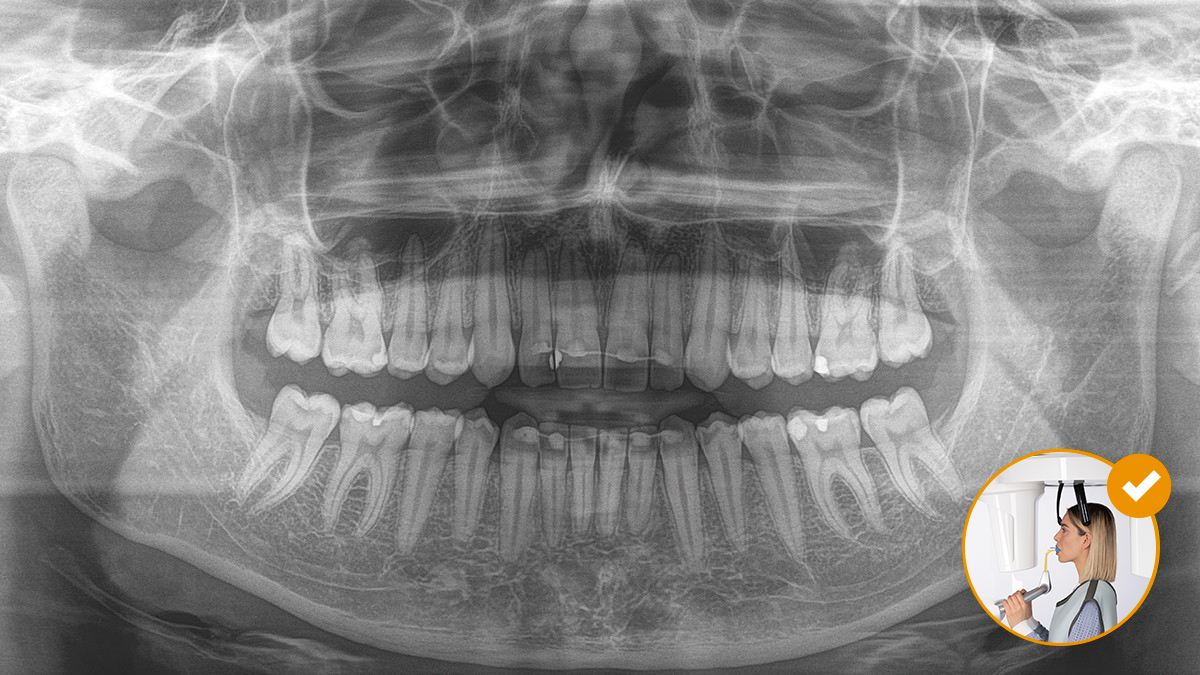

Ontspannen en aangename procedures zijn voor iedereen belangrijk, of het nu om patiënten gaat of het personeel. Het is voor iedereen fijn en motiverend als alles soepel en volgens plan verloopt. Met het gebruik van Orthophos of Axeos met Sidexis 4 krijgt u doelgerichte ondersteuning. De röntgensystemen zijn eenvoudig te gebruiken, maar bieden unieke diagnostische mogelijkheden. Dit waarborgt een positieve ervaring bij ieder aspect in het behandelingsproces.

Correcte patiëntpositionering leidt tot hoge beeldkwaliteit zodat een nauwkeurige diagnose wordt ondersteund en de patiëntervaring verbetert.

Dit is ons 10-puntenconcept voor een comfortabele patiëntpositionering en röntgenbeeldvorming. Het gaat primair om twee dingen: een hoge beeldkwaliteit en comfort voor zowel de patiënt als de assistent.